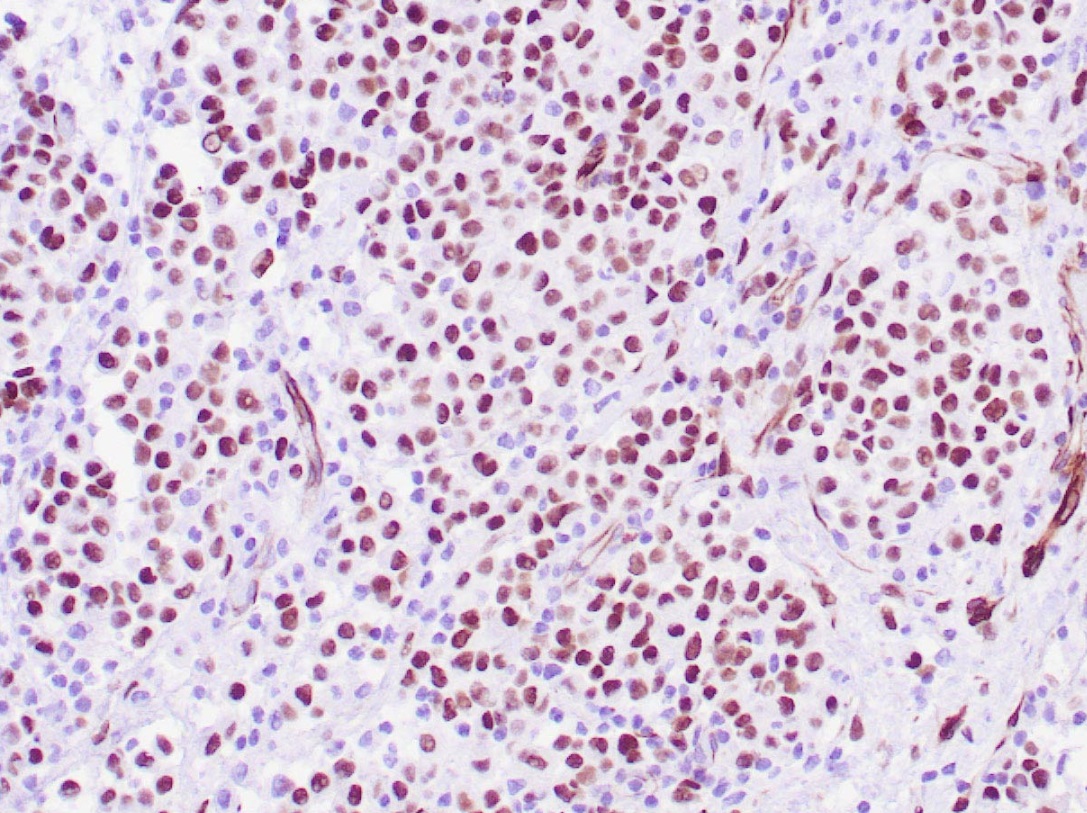

WILMS TUMOR (6F-H2)